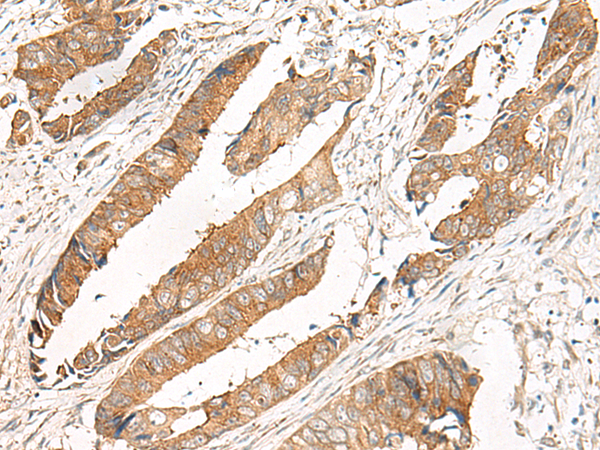

IHC positive control: |

Human cervical cancer and Human colorectal cancer |